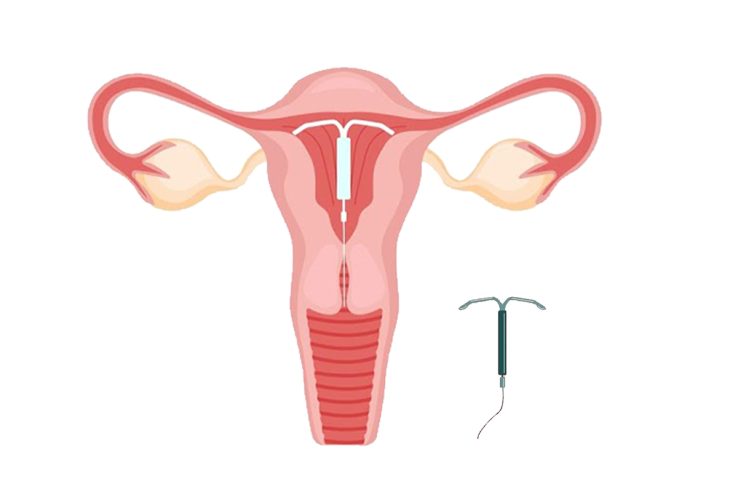

Infertility is a condition affecting millions of people worldwide, often in silence and solitude. For many couples, the path to parenthood is not always straightforward, and understanding how common infertility…